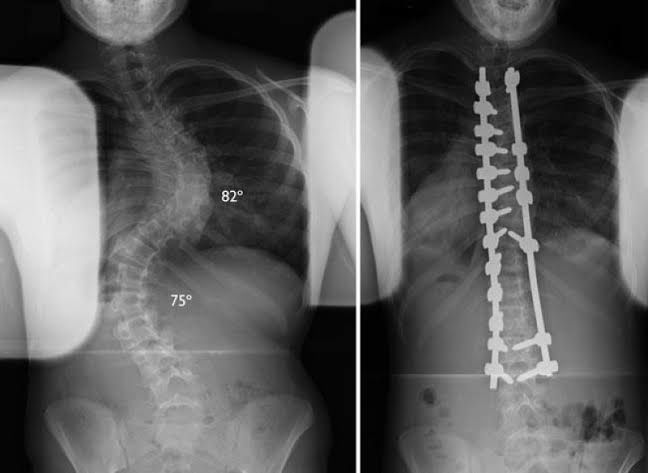

Escoliose

Deformidade da coluna que pode ocorrer por tendências genéticas, síndromes, doenças neurológicas ou desgaste intenso da coluna. Quando diagnosticada precocemente, deve ser acompanhada pois em alguns casos o uso de colete pode ser prescrito. Em casos onde há progressão da deformidade, compressão de nervos, dor intratável, pode-se instituir cirurgias corretivas para a deformidade.